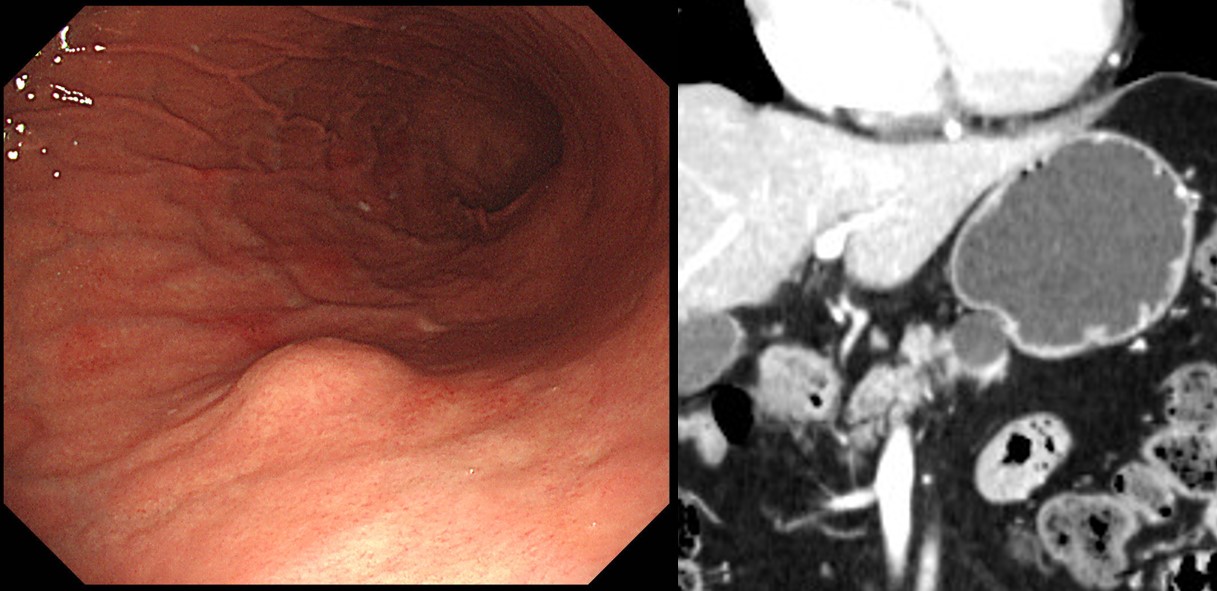

70 years old female was referred due to gastric SMT-like lesion. On the high body posterior wall, just below the cardia, a 3cm sized protruded lesion was seen. Extrinsic compression due to spleen was suspected. In the CT, splenomegaly, retroperitoneal lymph nodes were found. In the blood chemistry, total protein and globulin were elevated.

In the PET, hyperemetablic lymph nodes in the right supraclavicular, bilateral mediastinal, both pulmonary hilar, upper abdominal, and retroperitoneal area with splenomegaly were found.

EBUS-transbronchial needle biopsy showed low grade B-cell lymphoma, favoring extranodal marginal zone lymphoma of MALT. Chemotherapy (RCVP) was done and the followup PET and blood chemistry were normalized.